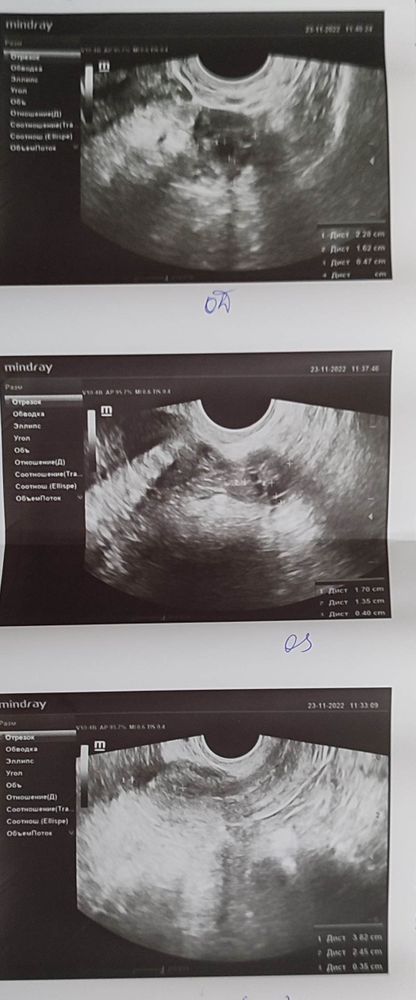

Там же врач тоже не увидела ничего плохого на осмотре, на УЗИ разглядела доминантный фолликул в правом яичнике и сказала ,что матка немного меньшего размера чем нужно, но это совсем не критично(результат платного УЗИ 1-2 фото) , так же сказала что можно пробовать забеременеть с этого цикла и посоветовала купить тесты на овуляцию, что я и сделала .

Далее 2 декабря я попала на УЗИ в ЖК(результат 3-4 фото), там узист сказала , что последствия овуляции она не видит, что возможно её совсем не было, матка у меня совсем маленькая и будут проблемы с зачатием и беременностью, посмотрела на результаты платного УЗИ, посмеялась и сказала что никакого доминантного фолликула она по этому УЗИ не видит, короче говоря очень меня расстроила и нагнала жути.

Тут объем матки 12-13 куб.см. Нормы от 40куб.см.